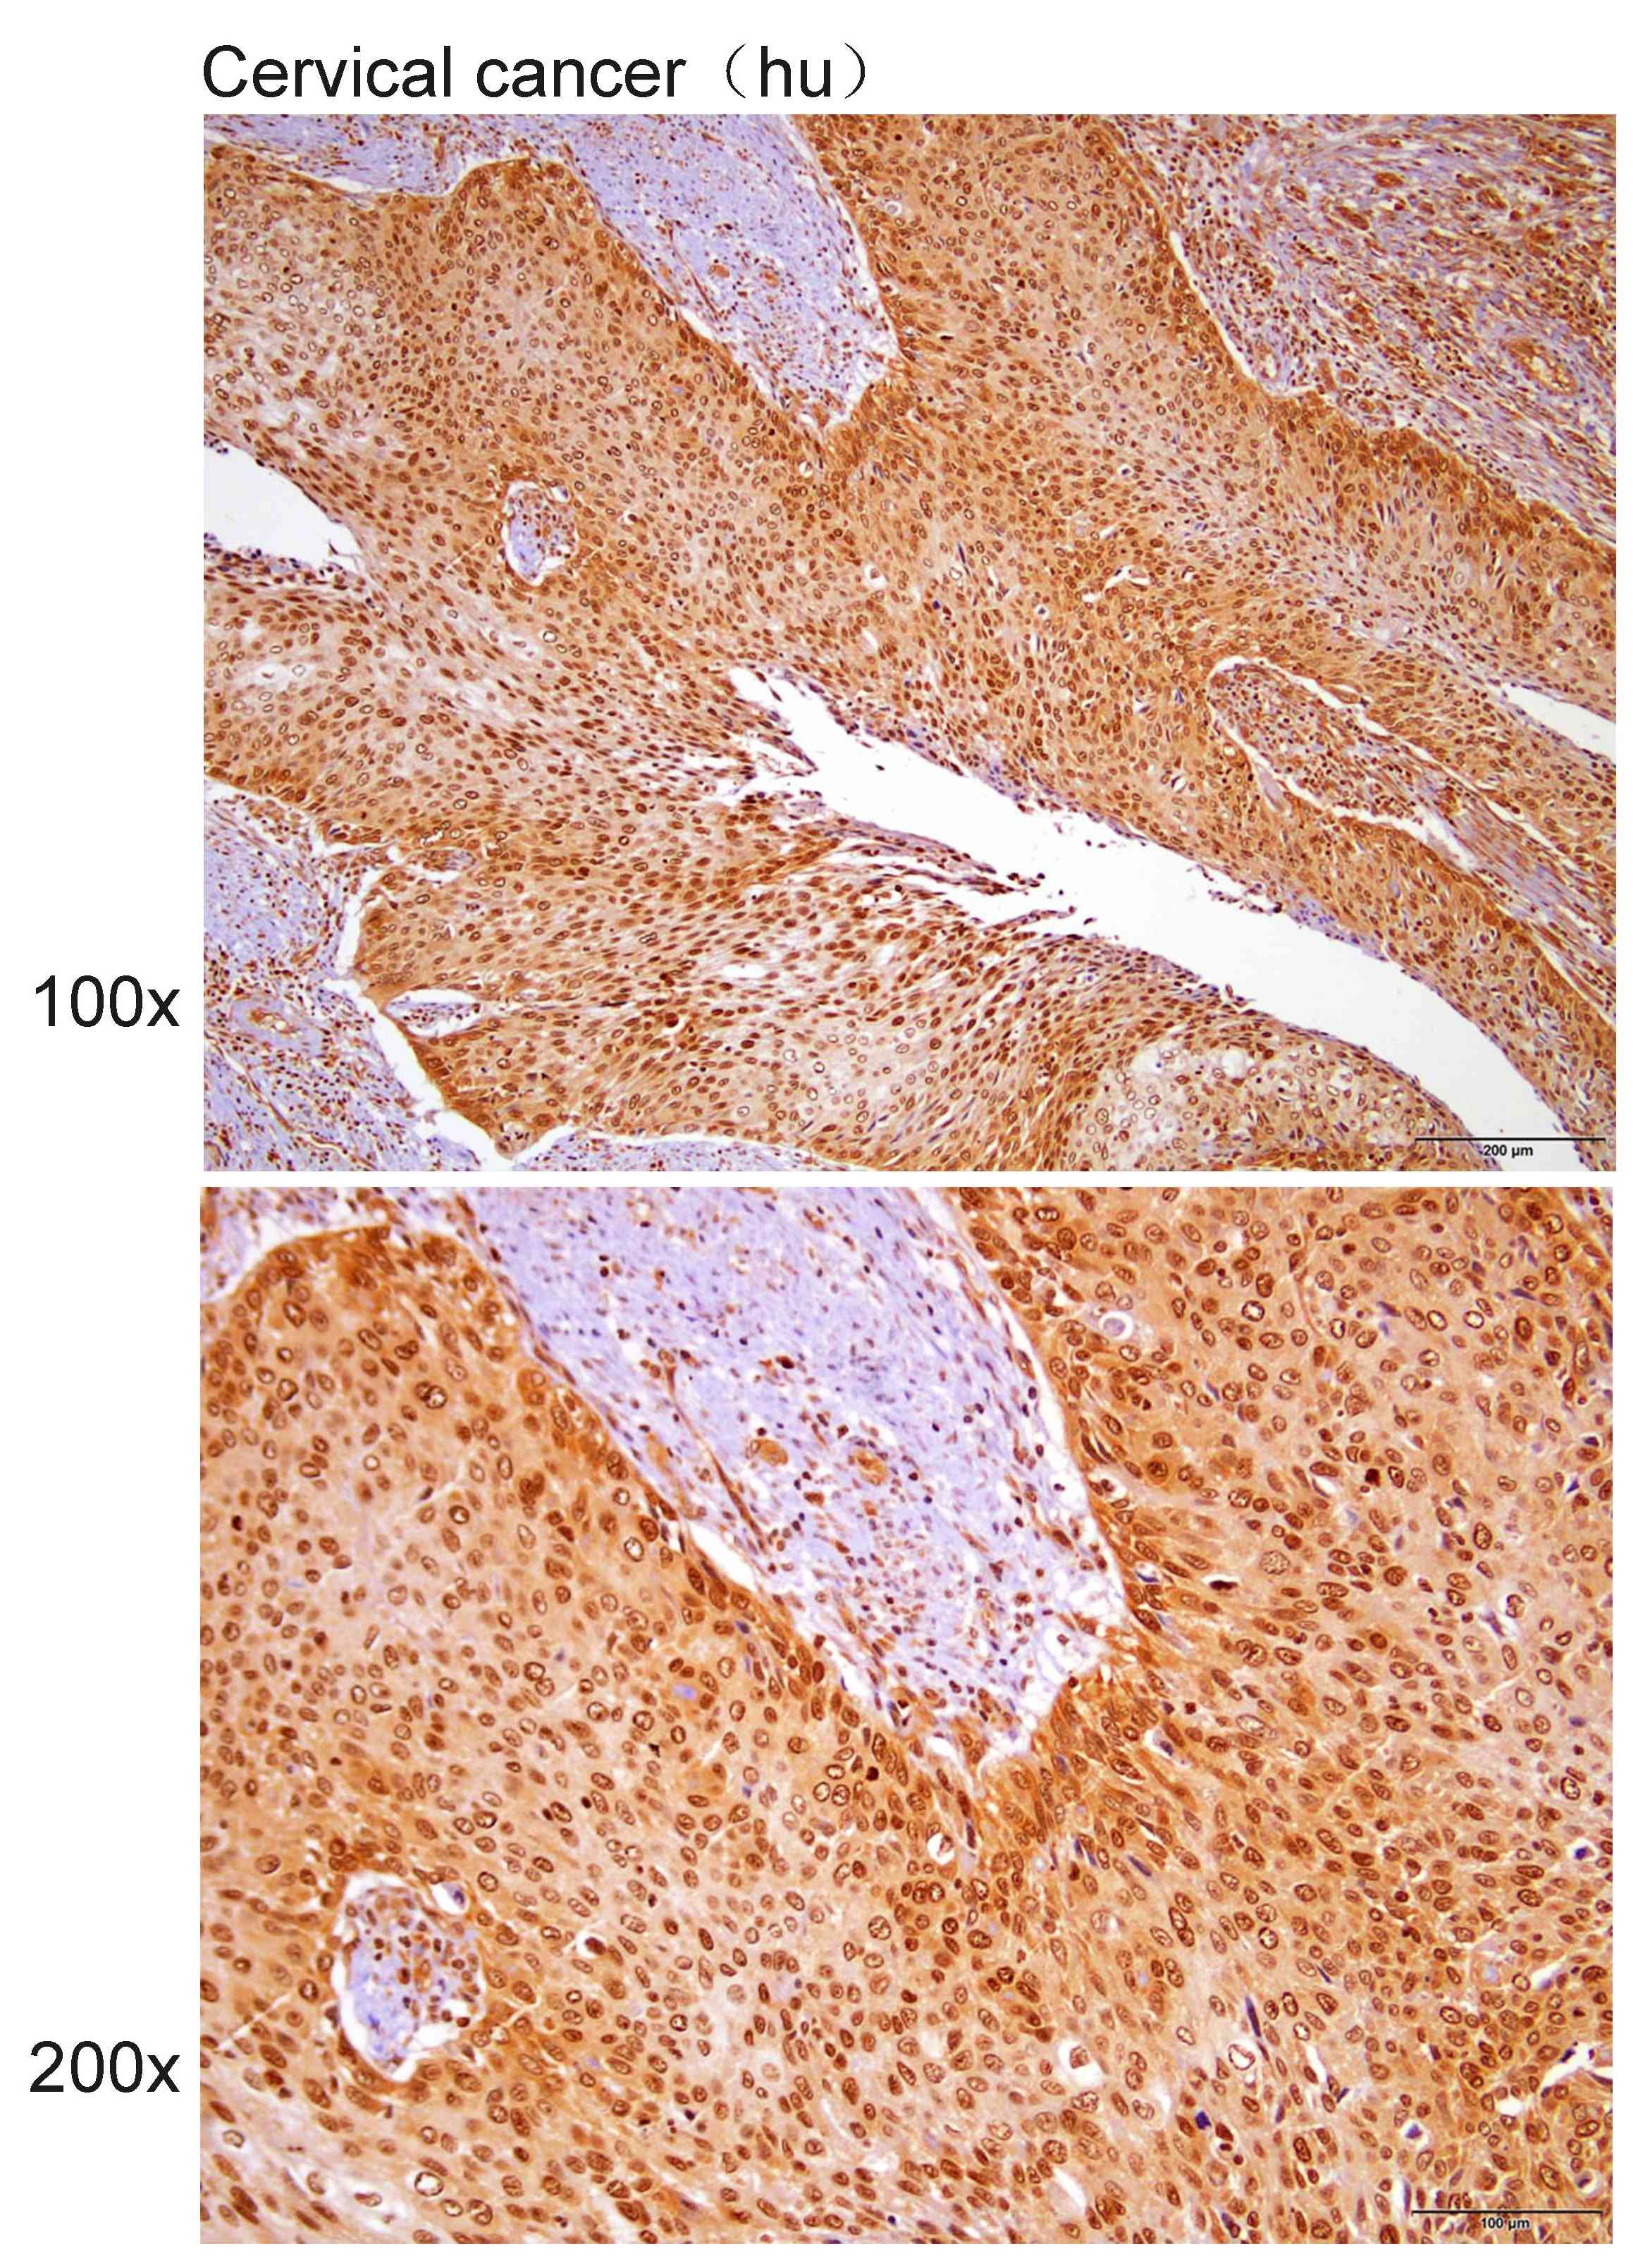

Immunohistochemistry?of?paraffin-embedded?Human Cervical cancer?with?RNF146 antibody diluted at 1:100